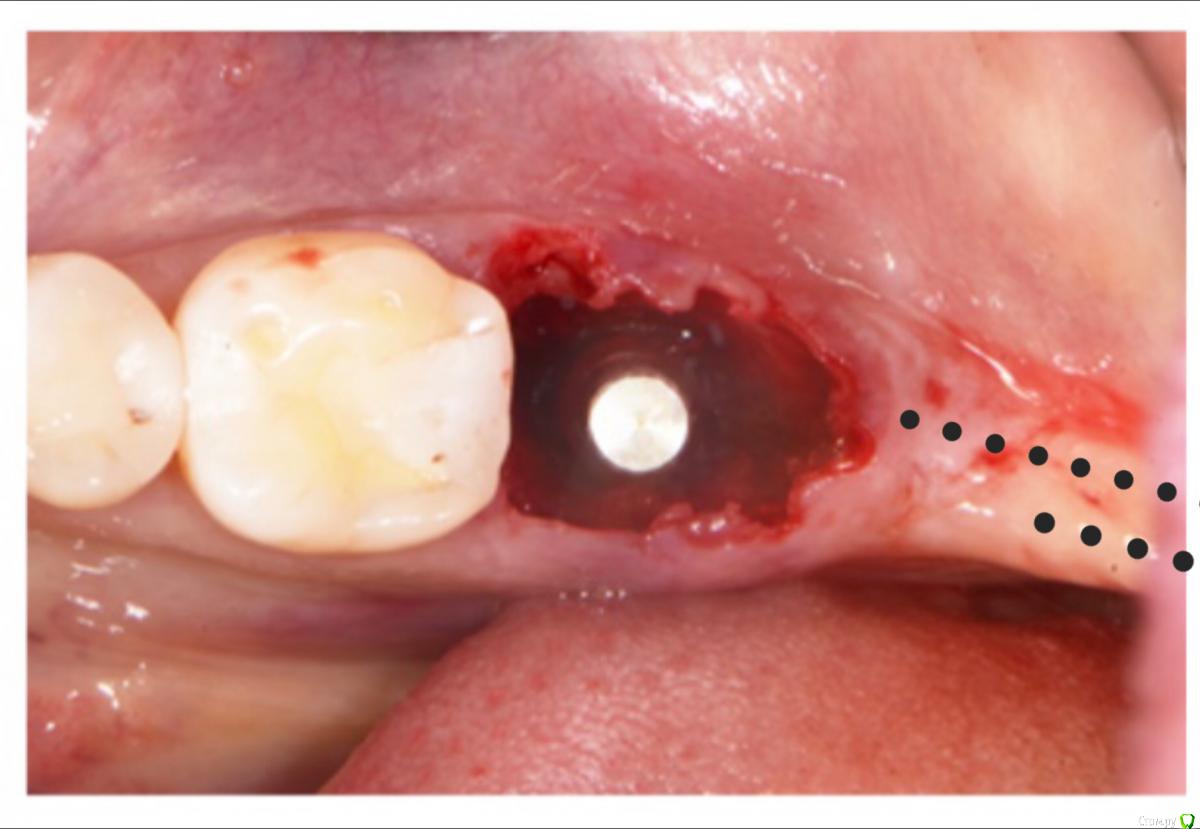

колесников Опубликовано 1 апреля, 2018 Поделиться Опубликовано 1 апреля, 2018 (изменено) Здравствуйте! Спасибо за упоминание! Вероятно автор не я и так уже кто-либо делал (Скляра я не читал ,как помните).Зона действительно сложная в плане дефицита прикреплённой слизистой ,сложности ее добавления . Есть трудность АСЛ,если производится отсроченно.Самого интересного кадра к сожалению нет,как выглядел лоскут,как выделялся,как перекидывался,где фиксировался. Отметил пунктирно на Вашем фото: разрез расщеплённый ,выделяя кератинизированую слизистую с гребня. Из правок: я бы выделил более длинный лоскут,пошёл бы дистально ретромолярно,чтобы дотянуть до 47го. Изменено 1 апреля, 2018 пользователем колесников Ссылка на комментарий

Irouil Опубликовано 1 апреля, 2018 Поделиться Опубликовано 1 апреля, 2018 Там дистально вестибулярный угол посмотрите, прикрепленки пол миллиметра. Чисто с формиком рецессия 100% Ссылка на комментарий

Карен Аванесов Опубликовано 1 апреля, 2018 Автор Поделиться Опубликовано 1 апреля, 2018 Фотографировать не очень было удобно, рассек до надкостницы, и выкроил два лоскута, чем то похожих на ласточкин хвост, одна часть вестибулярно, другая язычно. 1 Ссылка на комментарий